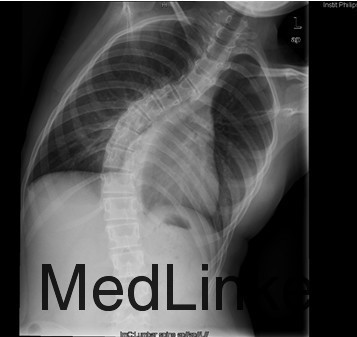

患者女,13岁,因“发现脊柱侧凸畸形4月”入院。患者4月前家长无意间发现胸背部脊柱侧凸,双肩不等高,无牛奶咖啡斑、无皮下结节,不伴活动耐力下降、气促、心悸、胸背痛、腰痛,日常活动及运动能力正常,在当地医院检查后建议手术治疗,到我院就诊,门诊以"特发性脊柱侧凸"收入住院。

查体:胸段脊柱向右侧凸,右侧胸廓后部凸起,剃刀背畸形,剃刀背高度2cm,右肩高,骨盆略向右倾斜,四肢及关节未见异常,未查见牛奶咖啡斑。脊柱各棘突及棘突旁无压痛及扣痛。胸腰部前屈、后伸及侧屈、侧旋范围正常,双下肢等长,未发现感觉减退区,四肢肌力5级,生理反射均正常引出,病理反射未引出。 辅查:X片示胸段脊柱以胸8为中心明显右侧弯畸形,胸段上段及腰段相应轻度左突侧弯。

初步诊断:特发性脊柱侧凸(Lenke:ⅡA ̄型) 诊疗计划: 拟经后路脊柱侧凸矫形+同种异体骨植骨+椎弓根螺钉内固定术术

术中见胸椎脊柱S形侧弯,肌肉韧性较差,棘突偏离中线,凹侧小关节退变明显,胸段脊柱以T8为中心明显右凸,T4为中心向左侧凸起,右侧剃刀背畸形。